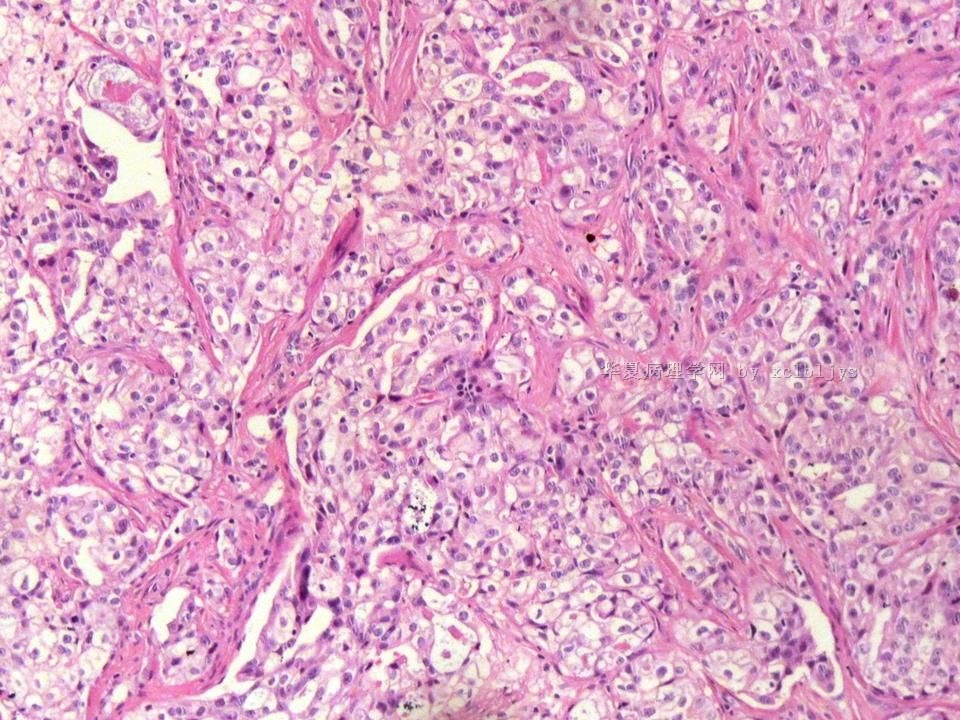

姓    名: ××× 性别:  男 年龄:  56

左锁骨上肿块三月余,手术切除。

蚕豆大肿块,包膜较完整,切面灰红色,质软。

• 左锁骨上肿块(IHC)图1

图1

转移癌

首先考虑甲状腺或肺来源

转移性腺癌。清查胃、肺等处有无原发灶。

转移性腺癌,请查消化道

免疫组化结果:TTF-1(+),CK7(+),CK20(-),TG(-)。临床近一步检查,肺未见肿块,左甲状腺发现肿块,目前仍未处理。

从形态结构看,有腺泡也有乳头结构,倾向转移性肺腺癌。